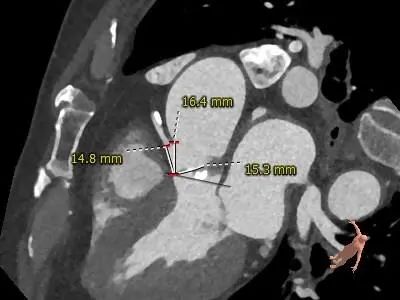

主动脉根部评估

CT 数据显示该患者为Type1型二叶式主动脉瓣

主动脉瓣瓣环周长72.5mm,周长径23.1mm

LVOT 周长 85.1mm,周长径27.1mm

SOV:31.1mm*33.6mm*31.6mm

STJ 周长 91.9mm

无冠瓣钙化严重,HU850:448mm³

瓣环水平夹角46度